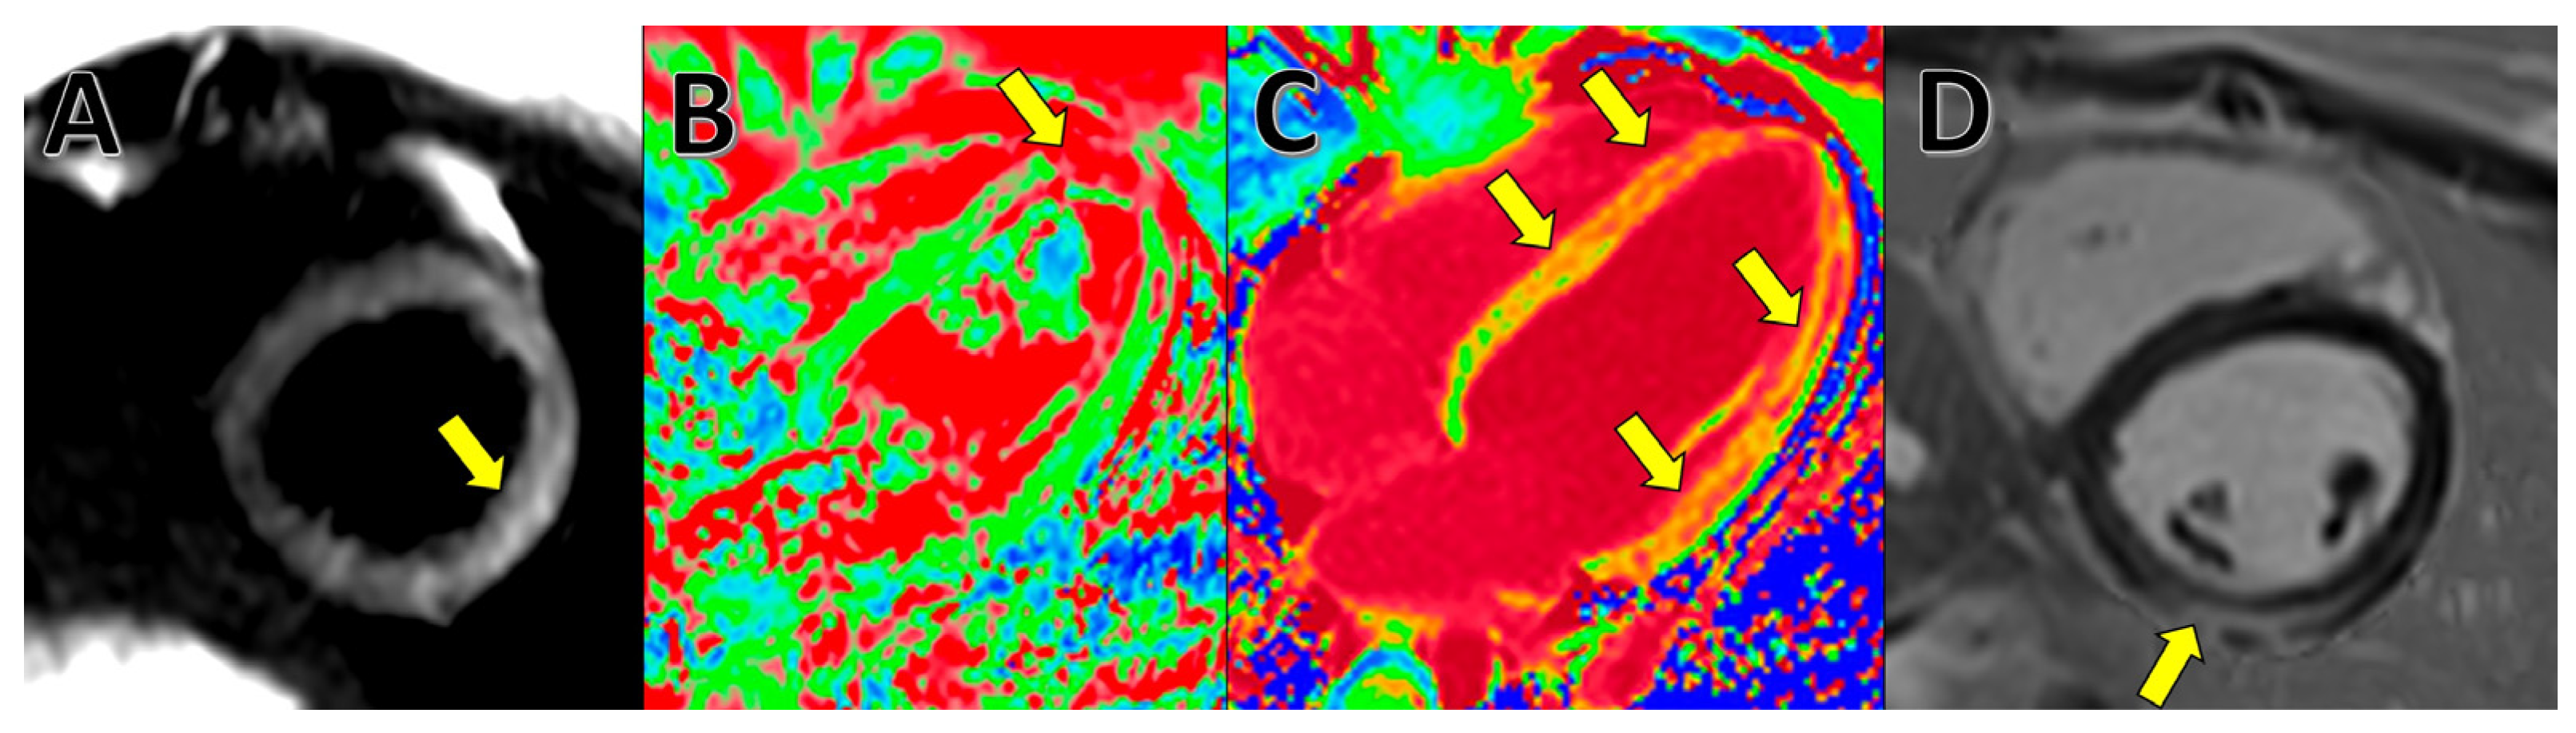

4. Cardiac Magnetic Resonance (CMR)